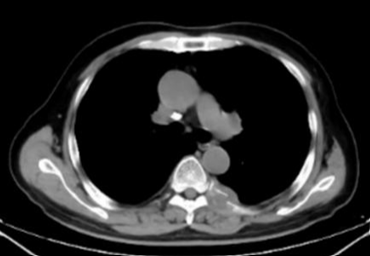

椎体压缩性骨折引起的腰痛患者,女性,66岁,因肺癌骨转移导致胸12椎体压缩性骨折,疼痛剧烈,翻身困难,无法下床活动。口服吗啡缓释片180 mg,q12h,口服吗啡恶心、便秘副反应明显,因咳血不宜加用非甾体消炎药。经过评估,决定采用椎体成形术。在局部麻醉下,通过经皮穿刺将骨水泥注入受损椎体。术后,患者的疼痛NRS评分从9分降至2分,第二天即可下床活动,生活质量得到显著改善(图1)。

1A

1B

图1:1A胸12椎体破坏,1B胸12椎体破坏被骨水泥填充